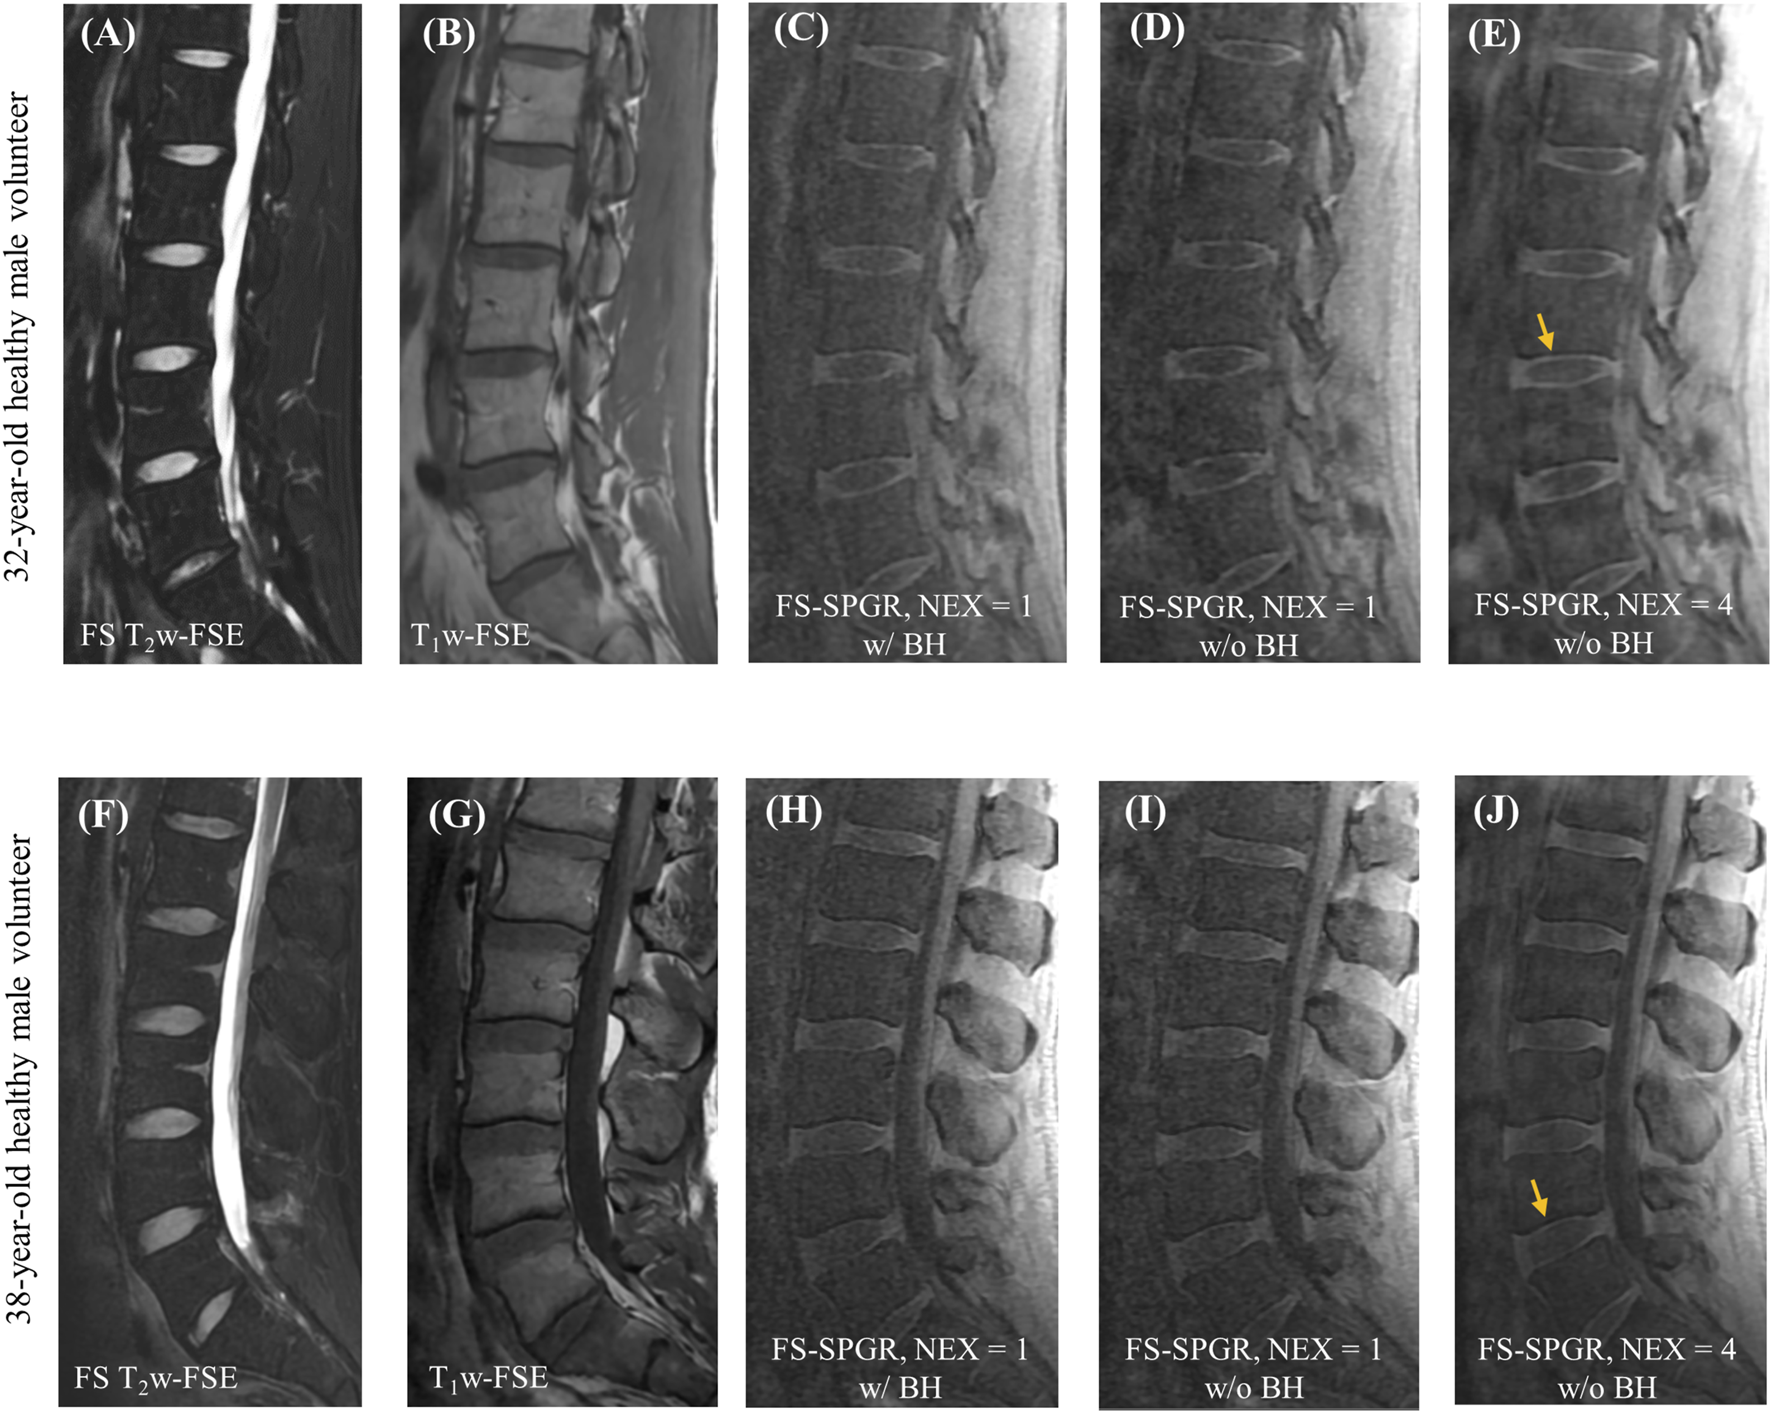

Figure 2 shows representative lumbar spine images acquired using the 3D FS-SPGR sequence from two different asymptomatic control subjects. The FS T2w-FSE and non-FS T1w-FSE images were unable to highlight the CEP signals due to their relatively long TE. The CEP regions were visually accentuated in the FS-SPGR images obtained with and without breath-hold. It is worth noting that although the breath-hold scan provided a sharper background compared to the free-breathing scan with NEX of 1, its SNR was relatively low. To improve SNR performance, NEX was increased to 4 for the free-breathing scans, yielding the highest quality CEP imaging.

FIGURE 2

Clinical FS T2w-FSE (A,F) and T1w-FSE (B,G) images as well as 3D FS-SPGR images (C–E,H–J) from a 32-year-old and a 38-year-old healthy male subject, respectively. Panels (C,H) and (D,I) show the single NEX FS-SPGR images with and without breath-hold (BH) for the two different controls respectively. To improve the SNR, NEX was increased to 4 for the free breathing scan (E,J), with yellow arrows indicating the high contrast CEP region.